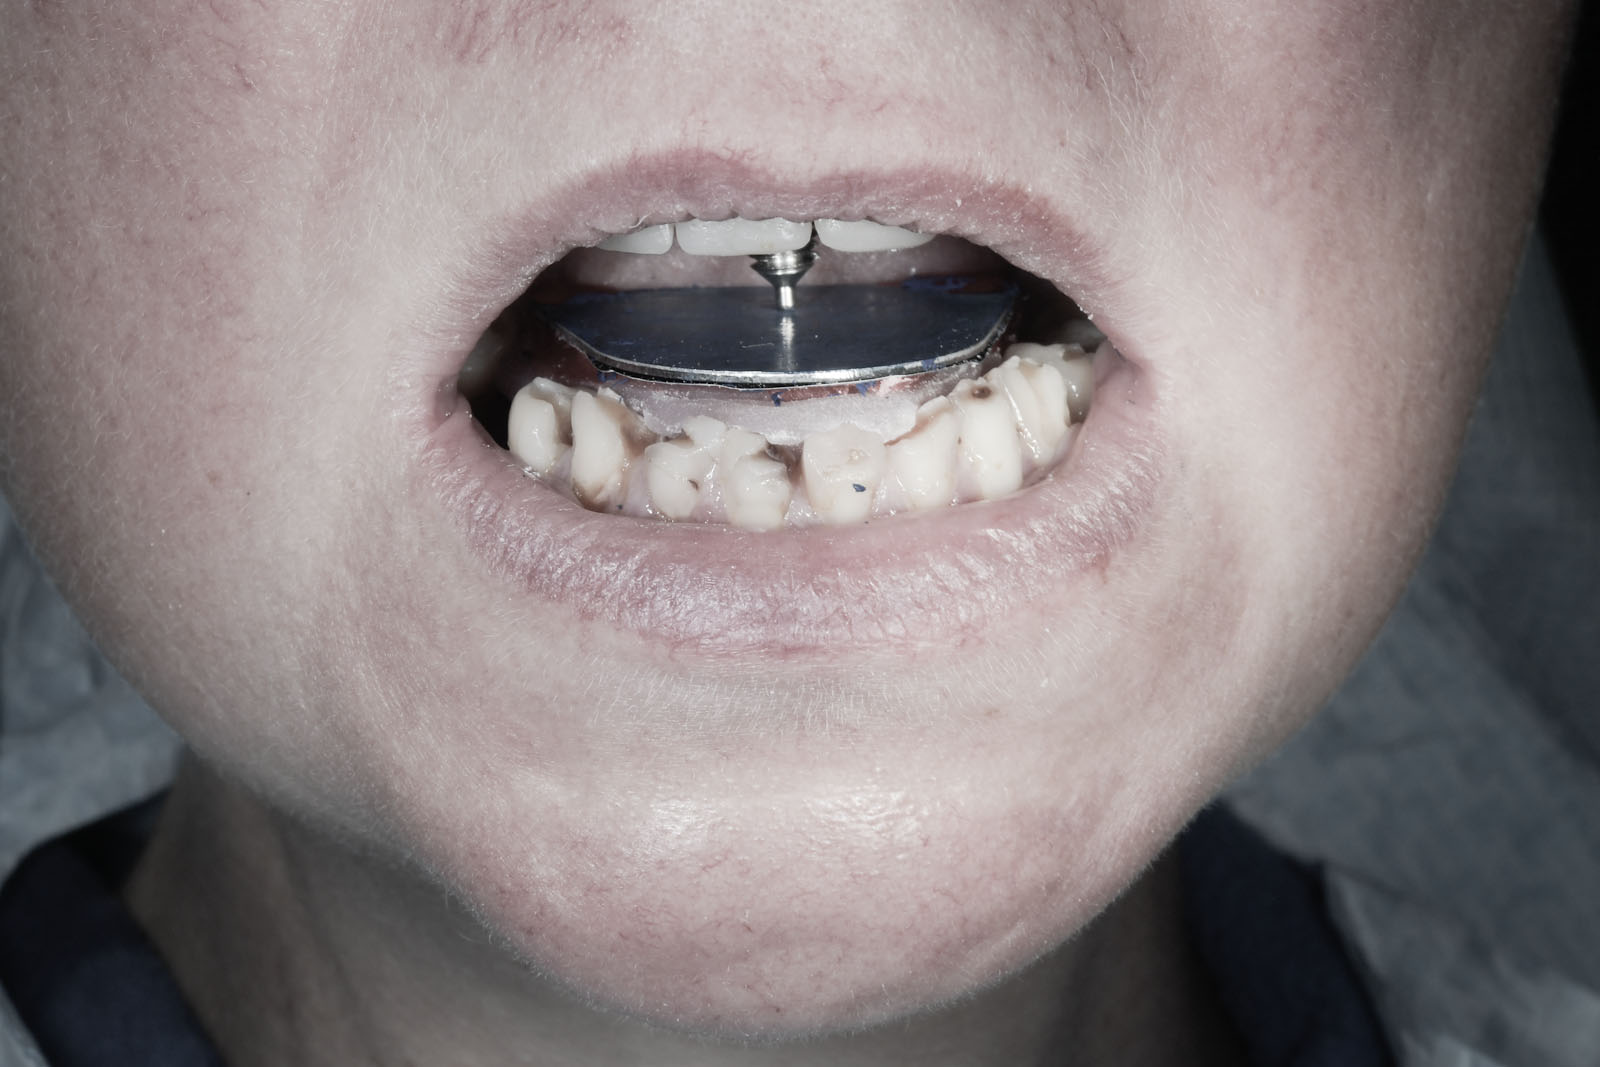

W celu ustalenia wzajemnej relacji żuchwy i szczęki Gerber poleca rejestrację z użyciem centralnego sztyftu podpierającego, który zapewnia równomierne obciążenie podłoża protetycznego i stawów skroniowo-żuchwowych, a także ułatwia centralne ułożenie głów stawowych dzięki trójpunktowemu podparciu żuchwy w stosunku do czaszki.

W pierwszym etapie wykonuje się modele robocze, które są montowane w opracowanym przez prof. Gerbera artykulatorze. Tak zwany condylator pozwala na symulację trójwymiarowych ruchów głów żuchwy. Pozwala na zweryfikowanie poprawności relacji pomiędzy łukiem zębowym górnym a dolnym. Po dokładnym zbadaniu funkcji i morfologii stawu sż, wykonaniu pomiarów oraz ocenie stanu zdrowia zębów zostaje opracowany indywidualny plan leczenia zgodny z uwarunkowaniami pacjenta.

Dzięki zastosowaniu łuku twarzowego możliwy jest pomiar kątów nachylenia torów przesuwania głów żuchwy. Pozwala to na zamontowanie modeli gipsowych w stosunku do stawów skroniowo-żuchwowych i płaszczyzny Campera (linii uszno-nosowej) orientacyjnej w widoku z profilu. Ma to na celu odtworzenie prawidłowej okluzji, czyli odpowiedniej pozycji stykania się zębów górnych z dolnymi.